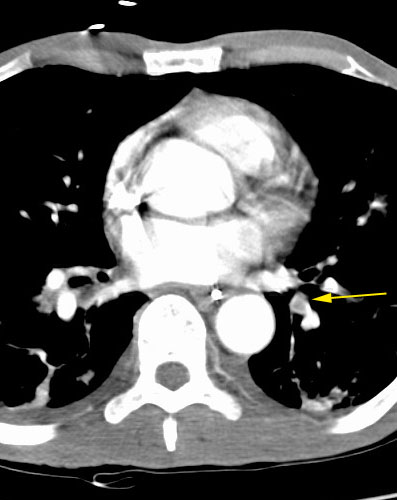

Pulmonary emboli in a lymphoma patient with SVC thrombosis

By

Scott Williams

August 28, 2001